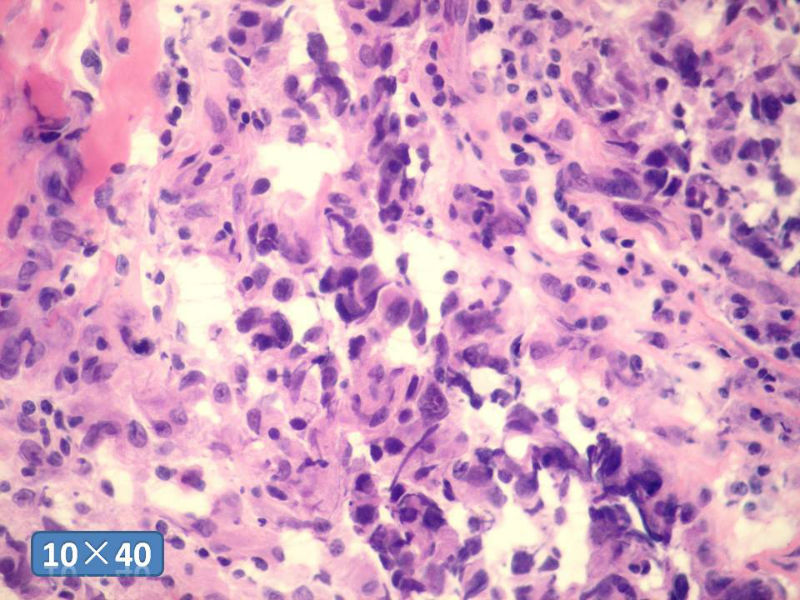

女性,50岁,乳腺肿物,冰冻切片(图1-25)

HE